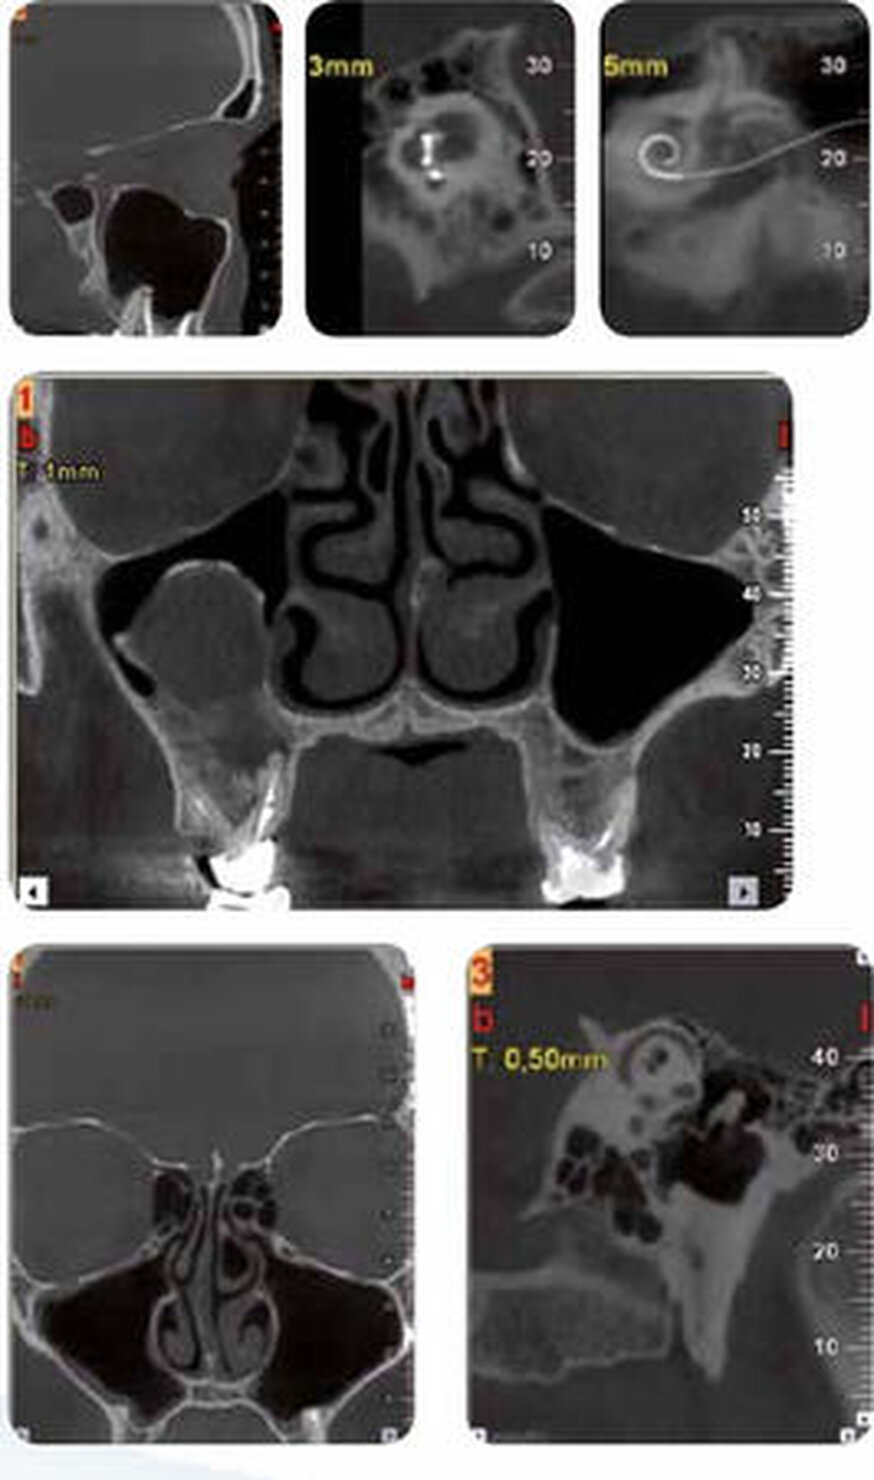

ATM

Le apparecchiature NewTom portano a un nuovo livello qualitativo e quantitativo la rappresentazione dell’articolazione temporo-mandibolare. I tagli sagittali e coronali forniscono un’ottima rappresentazione dello spazio articolare e permettono l’individuazione di eventuali patologie. Le immagini 3D ottenibili danno prova di un’alta qualità e accuratezza nella rappresentazione anatomica dell’ATM e della zona cervicale. Le immagini panoramiche, adatte ad uno screening iniziale, mettono a disposizione informazioni ortodontiche importanti, come la differenza tra l’altezza del condilo e quella del ramo della mandibola o di altre patologie dentali.

ORL

Con una singola scansione è possibile visualizzare chiaramente tutte le vie aeree, le strutture dell’orecchio, i seni nasali e le rocche petrose. La maggior parte degli esami effettuati utilizzando le TAC convenzionali può essere realizzata anche con NewTom, che metterà in risalto un maggior numero di dettagli e, grazie all’utilizzo di parametri radiologici adeguati, eviterà dosaggi sovrastimati al paziente.